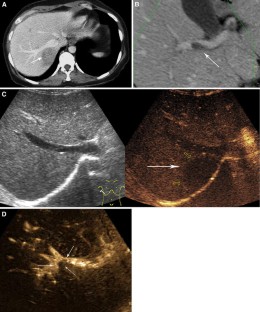

Fig. 2